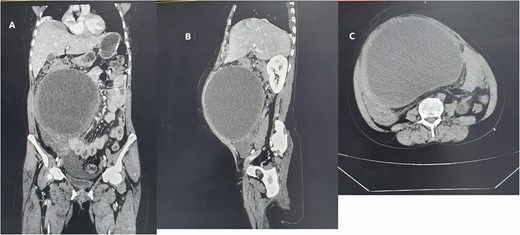

Laboratory parameters were in the normal range. Abdominopelvic ultrasound suggested an intraabdominal cyst that extends to the pelvis with small free fluid collection adjacent to the cyst. Abdominopelvic computed tomography with contrast showed a large, thick-walled mesenteric cystic lesion measuring 19.6 × 17.6 × 13 cm, likely of ovarian origin. The cyst occupied the right upper and lower abdominal quadrants, crossing the midline. It extends from the subhepatic region at the T12 to the S1 level of the vertebrae (Fig. 1). Since the organ of origin was difficult to settle, the gynecology department was consulted to overview the case and jointly manage the patient.

Homogenous hypoattenuating large unilocular cystic mass occupying abdominopelvic cavity with some areas of high attenuating of different viscosity and ovarian vascular pedicle sign as an organ of origin measuring 19.6 × 17.6 × 13 cm (green arrow) (A) coronal enhanced abdominal CT scan (B) enhanced sagittal abdominal CT scan (C) non enhanced upper abdomen axial CT scan.